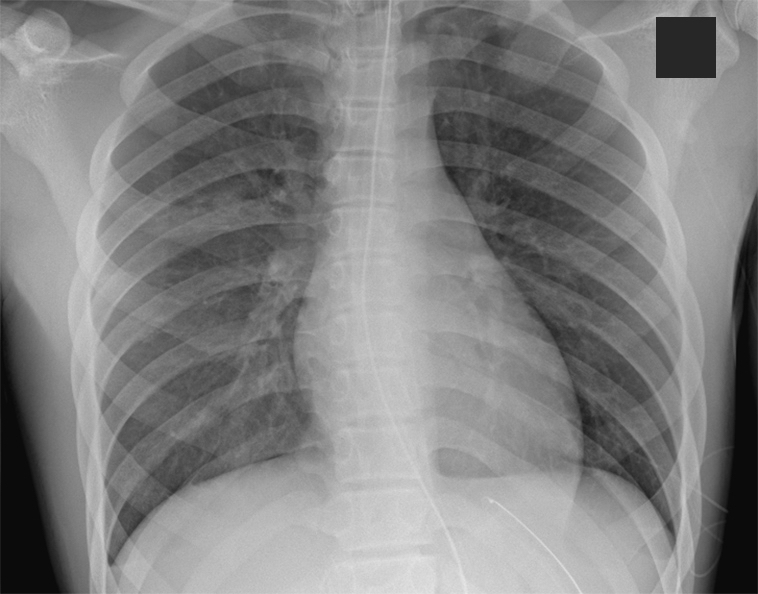

A chest radiography scan showed concern for pulmonary edema (Figure 1). He was placed on bilevel positive airway pressure (BiPAP) at 14/7 cmH20. After another cough with blood-tinged sputum, he was reintubated to protect his airway given the concern for pulmonary hemorrhage. The patient’s average heart rate and blood pressure pre- and post-naloxone administration were 78 bpm and 157/88 mmHg and 83 bpm and 119/75 mmHg, respectively.

Figure 1. Development of bilateral pulmonary edema after administration of naloxone (total 200 mcg).